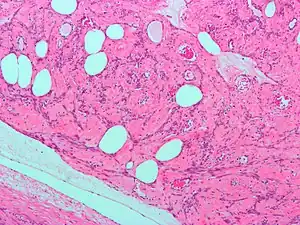

Fibroids are a type of uterine leiomyoma. Fibroids grossly appear as round, well circumscribed (but not encapsulated), solid nodules that are white or tan, and show whorled appearance on histological section. The size varies, from microscopic to lesions of considerable size. Typically lesions the size of a grapefruit or bigger are felt by the patient herself through the abdominal wall.[1]

Microscopically, tumor cells resemble normal cells (elongated, spindle-shaped, with a cigar-shaped nucleus) and form bundles with different directions (whorled). These cells are uniform in size and shape, with scarce mitoses. There are three benign variants: bizarre (atypical); cellular; and mitotically active.

Giant leiomiyomas almost filling the abdomen. Histopathology of uterine fibroids typically show smooth muscle in a whorled (fascicular) pattern.[32]

Histopathology of uterine fibroids typically show smooth muscle in a whorled (fascicular) pattern.[32].jpg.webp) This variant of Van Gieson's stain distinguishes muscle (yellow) from connective tissue (red)

This variant of Van Gieson's stain distinguishes muscle (yellow) from connective tissue (red)